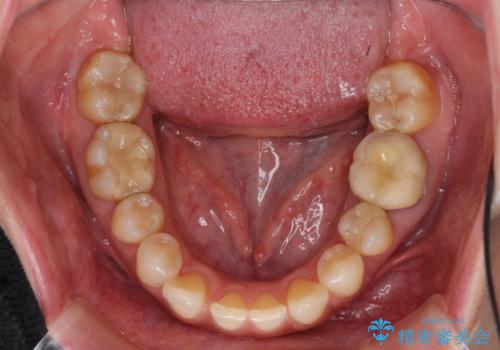

下顎2前歯の欠損 インビザラインによる抜歯矯正

- 下顎前歯欠損による歯列不正を気にして来院された患者様です。

下顎の歯列が小さく、下顎前歯が隠れてしまう過蓋咬合(ディープバイト)であったため、